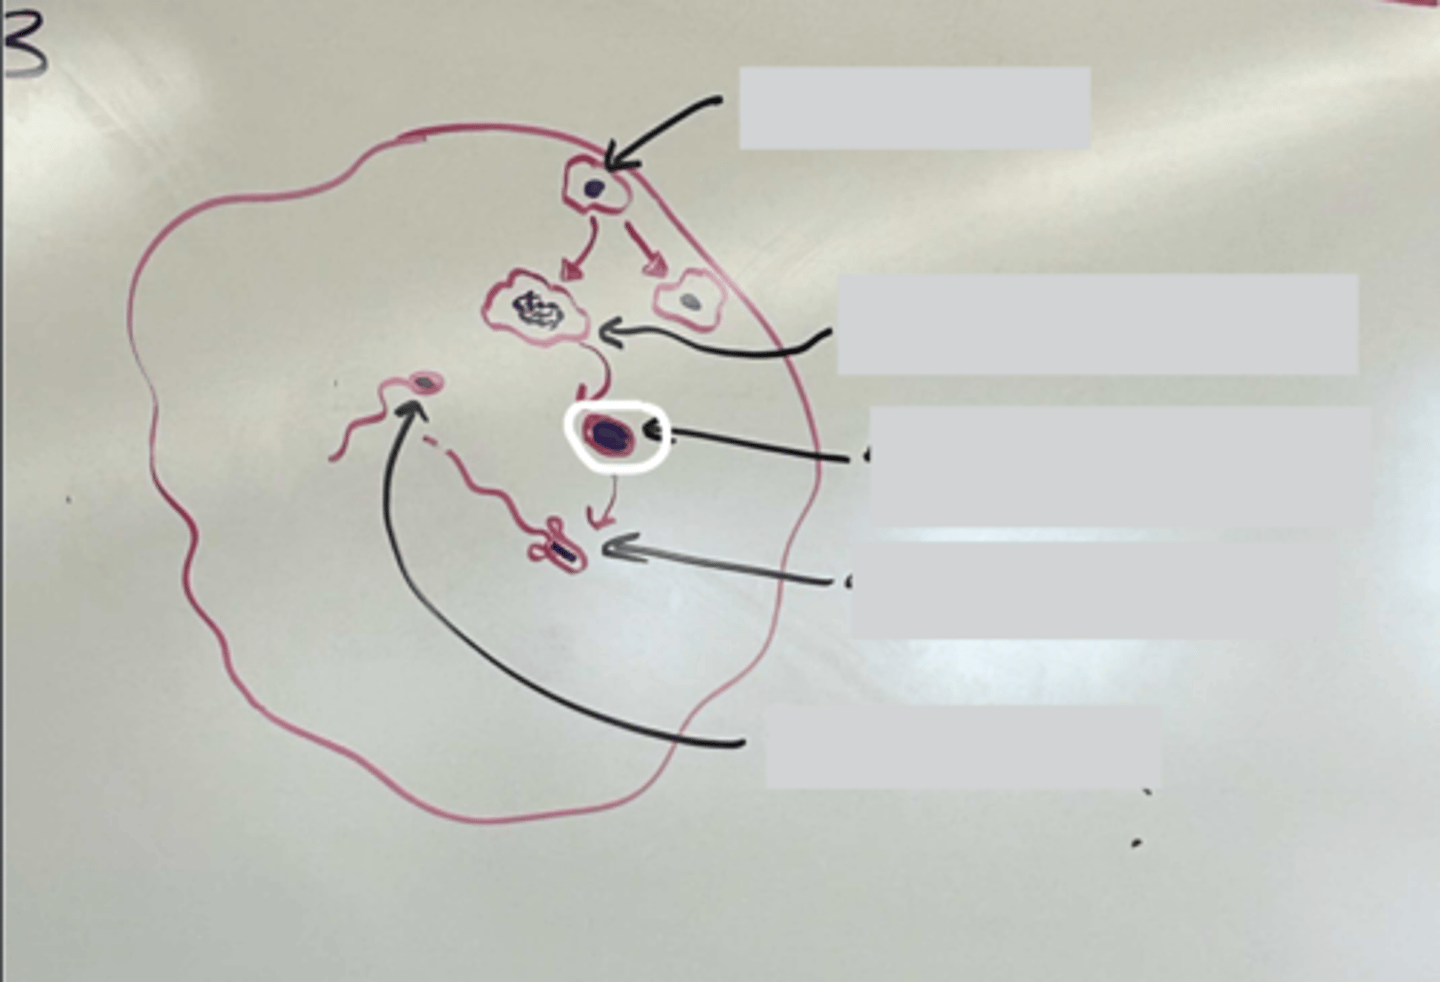

Spermatogenesis

Spermatogenesis

Spermatogonia

Primary spermatocyte

Spermatogonia

Spermatid (early)

Primary spermatocyte

Spermatid (late)

Spermatid (early)

Spermatozoon

Spermatid (late)

Spermatozoa